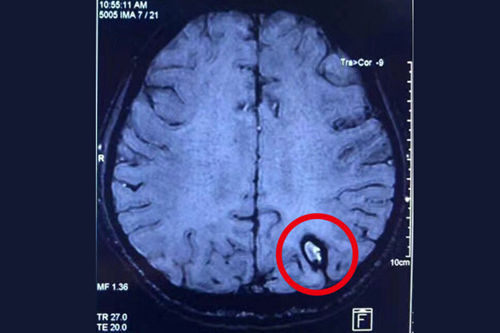

患者術(shù)前的磁共振影像: 紅圈處為顱內(nèi)海綿狀血管瘤病灶